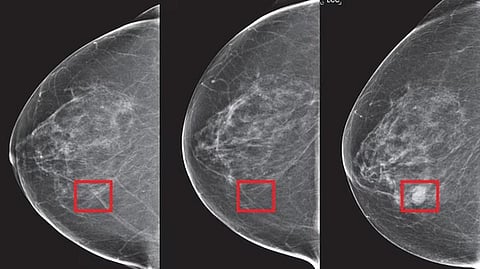

அமெரிக்காவில் 8 பெண்களில் ஒருவருக்கு மார்பக புற்றுநோய் பாதிப்பு ஏற்படுகிறது. மேமோகிராம் மூலம் மார்பக புற்றுநோயை கண்டறிய முடியும். ஆனால் சில நேரங்களில் மேமோகிராம் மூலம் மருத்துவர்களால் முன்கூட்டியே மார்பக புற்றுநோயை கண்டறிய முடியவில்லை.

இதற்கு தீர்வு காணும் வகையில் ‘மிராய்' என்ற பெயரில்புதிய செயற்கை நுண்ணறிவுதொழில்நுட்பம் கண்டுபிடிக்கப்பட்டு உள்ளது. இந்த புதிய தொழில்நுட்பத்தின்படி 5 ஆண்டுகளுக்கு முன்பே மார்பக புற்றுநோயை கண்டறிய முடியும். இதன்மூலம் ஆரம்ப நிலையிலேயே சிகிச்சை அளிக்க முடியும்.